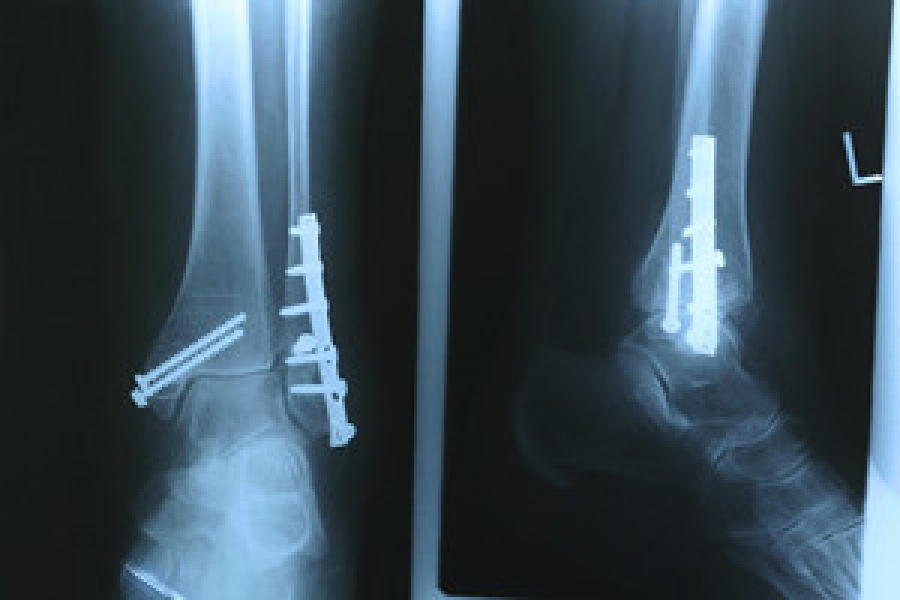

Most Missed Case Calcaneal Fracture » Wisdom in Diagnostic Imaging

From widi.xray.ufl.edu

Most Missed Case Calcaneal Fracture » Wisdom in Diagnostic Imaging Explain Why A Stress Fracture Is Sometimes Missed In A Standard X-Ray Stress views may be necessary to show injury to the ankle mortise or syndesmotic diastasis. Imaging examinations are fundamental for diagnosing, prognosing and following up stress fractures. A fracture may be missed because it is radiologically invisible or equivocal: When there is high clinical suspicion. Doctors can sometimes diagnose a stress fracture from a medical history and a physical exam,. Explain Why A Stress Fracture Is Sometimes Missed In A Standard X-Ray.